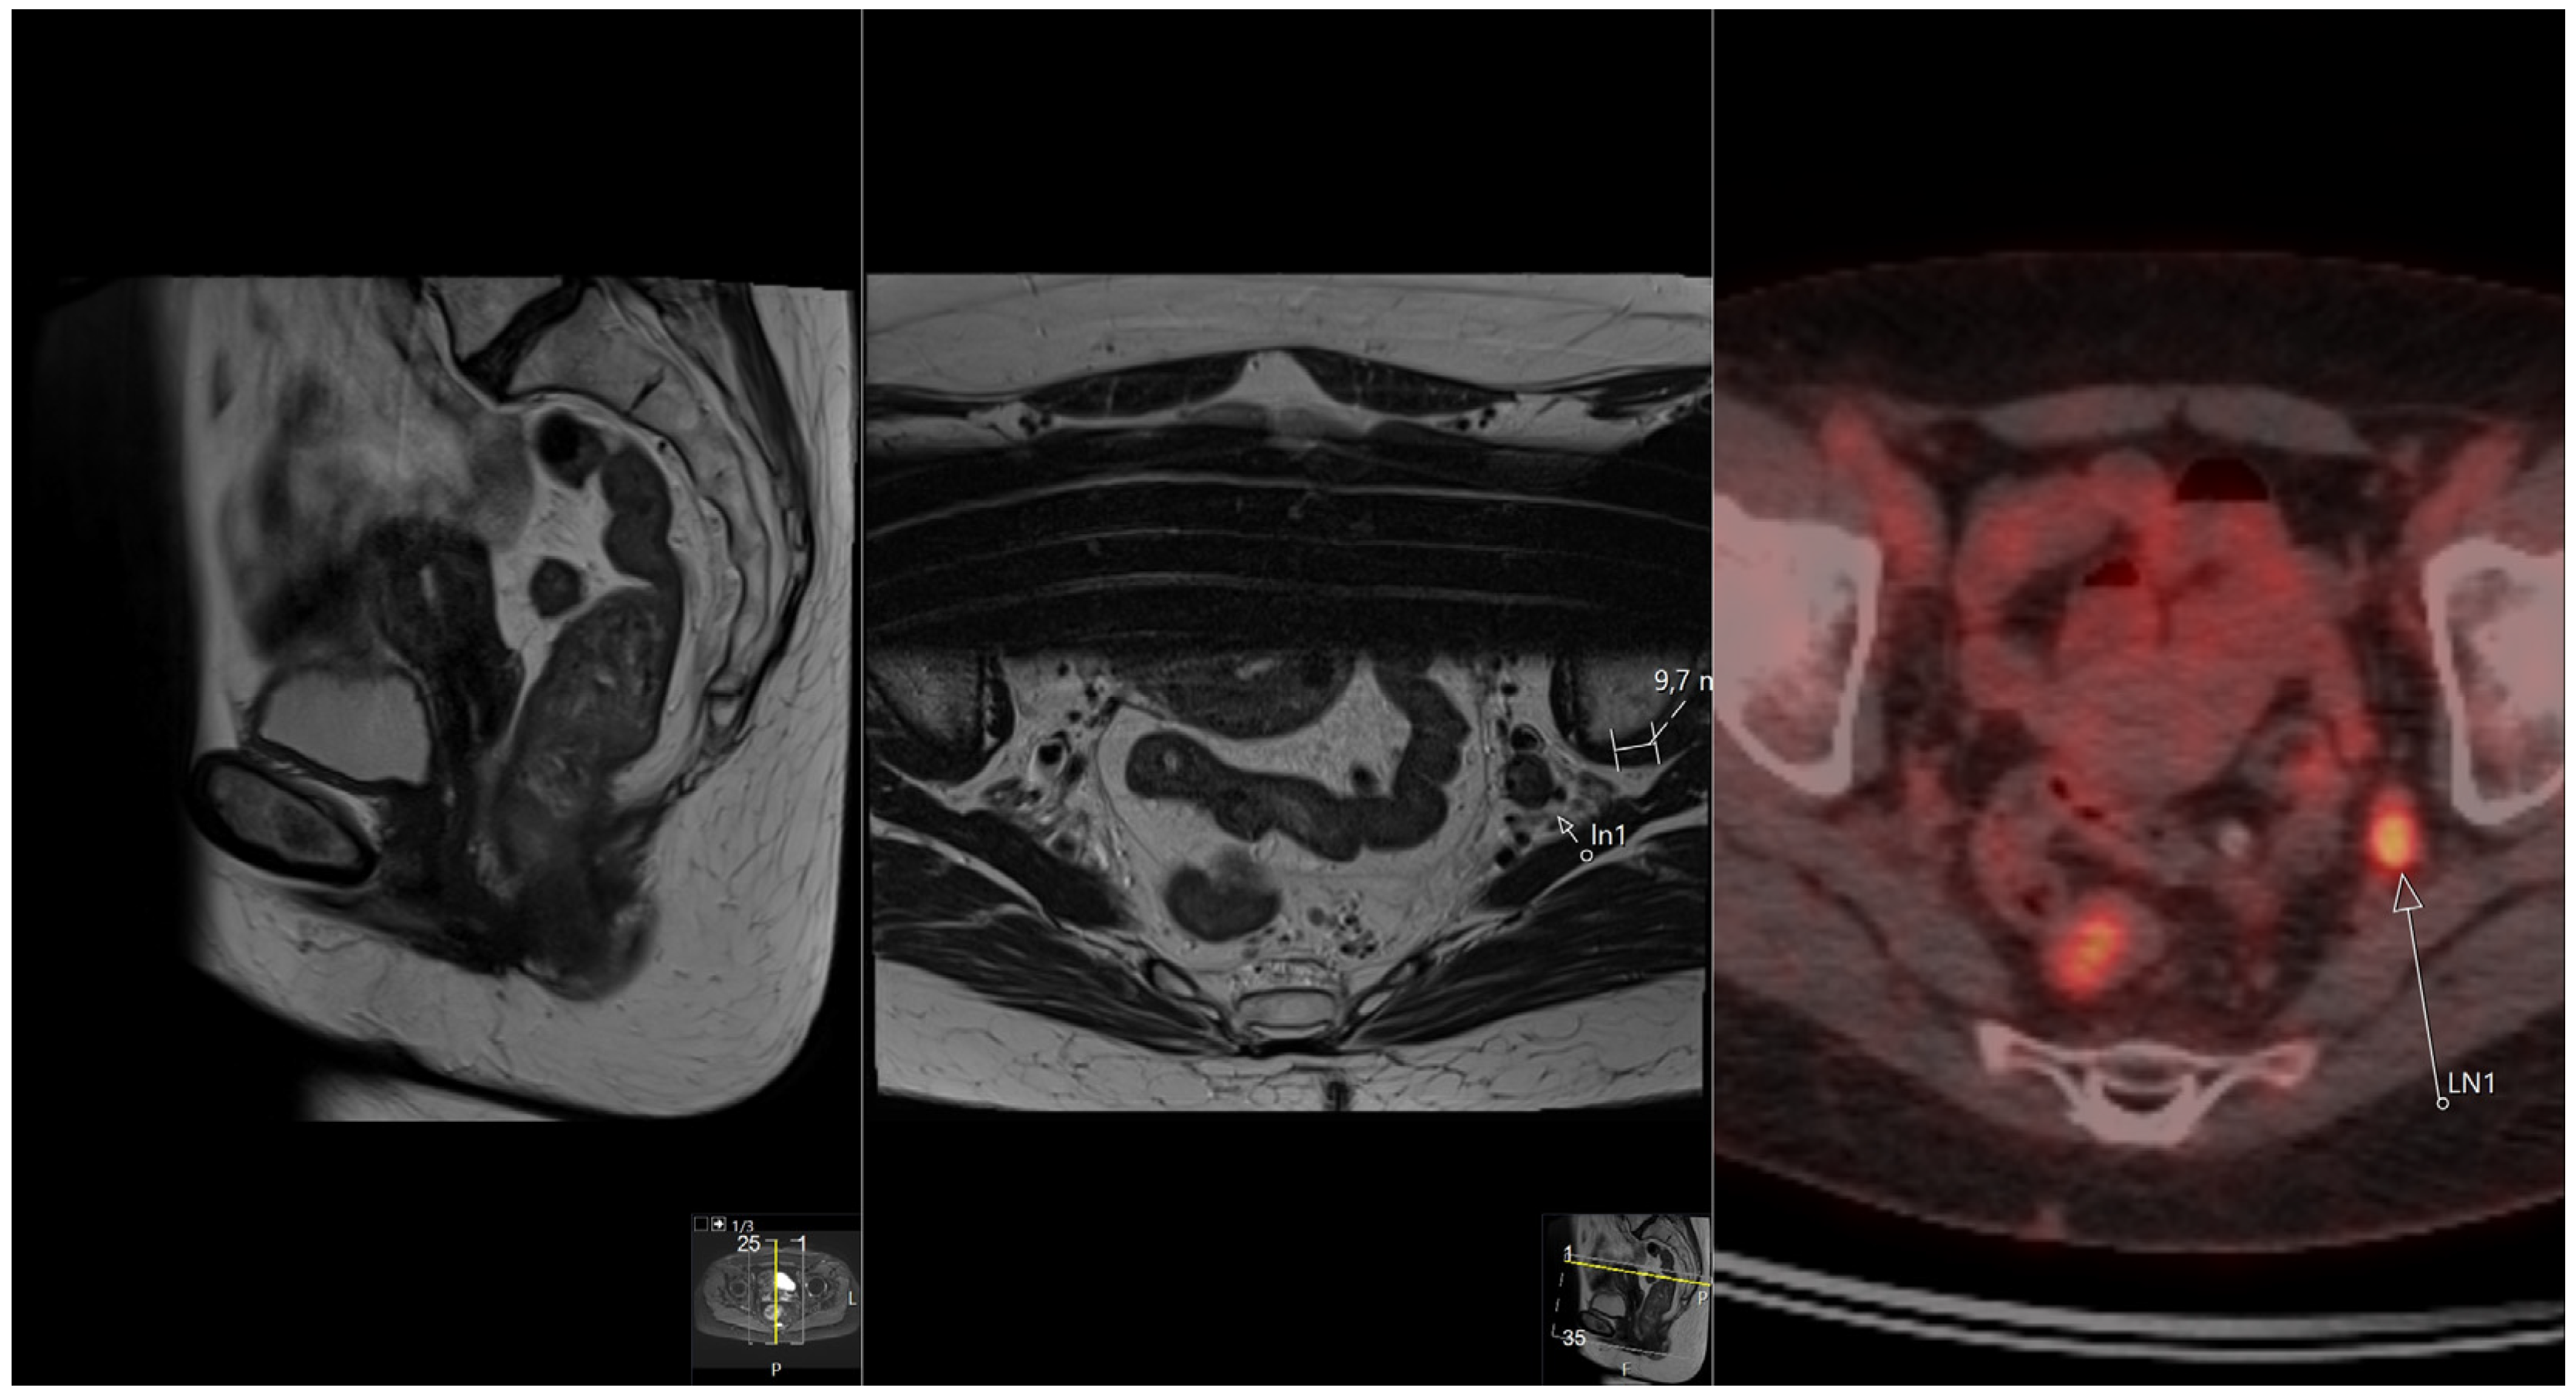

The Additional Role of F18-FDG PET/CT in Characterizing MRI-Diagnosed Tumor Deposits in Locally Advanced Rectal Cancer

2.3.2. F18-FDG PET/CT

2.3.3. Correlating MRI and F18-FDG PET/CT Images